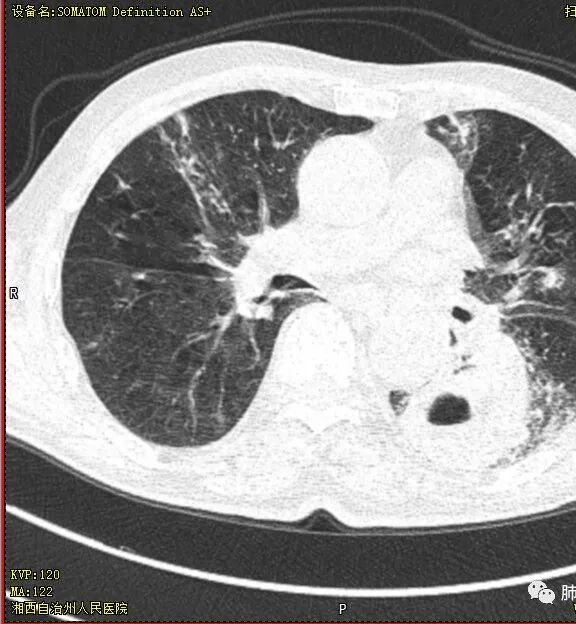

晨读 双肺多发斑片、斑点影,可见树芽征,支气管播散,右肺上叶小空洞,左肺下叶厚壁空洞,内壁较光整,有浅液平,右下叶背段支气管变窄,不均匀强化。结合临床考虑结核并感染,待排除合并肺癌可能。

晨读:老年男性患者,痰中带血伴间断发热2周,体温39.4℃,白细胞、中性粒细胞,CRP增高,Tspot阳性,胸部CT:双肺病变,左肺下叶背段大片实变密度影,边界模糊,内部见空洞形成,空洞内壁总体光滑,有气液平,增强扫描轻度不均匀强化,一月后复查空洞消失,实变影吸收减少,考虑感染性病变,结核伴肺脓肿。

老年慢性长期吸烟,痰中带血伴发高热。左下肺大片不均质实变里可见一含气液平厚壁空洞,内壁有坏死物残留,增强可空洞壁明显强化轮廓显示清晰,空洞位于肺门侧,近端支气管壁不规则增厚。两肺散在斑片状影,并见小树芽。18号复查肺窗空洞显示不清,20号用了俯卧位扫描,液体向下流动空洞又显示出来了。左下肺病灶有变小,还是考虑感染性病变,结核合并感染,鉴别鳞癌。

老年患者。左肺下叶厚壁空洞,有液平面。空洞内壁较为光整。病灶的内侧见支气管节段性的变窄扭曲。两肺内,弥漫性的广泛性的播散病灶。考虑感染性病变。肺结核并空洞形成两肺内播散。鉴别诊断-左肺下叶鳞癌。

双肺多发结节影,树芽征,小叶中心分布,左肺下叶不规则空洞,洞内壁光滑,见液平,洞壁似与支气管相通,增强扫描明显强化,可见血管造影征。三周左右复查空洞明显缩小。

首先双肺多灶多形态病灶,考虑结核,聚焦左下肺病灶,空洞,内壁尚光整,有明显液化坏死,增强无明显强化,壁内可见支气管充气征,复查后空洞缩小,首先考虑良性,结核伴脓肿,鉴别鳞癌

胸部CT:双肺多发小斑片、树芽、索条灶,左下肺大片不均质实变,远肺门侧厚壁空洞,气液平,内壁有坏死物残留,增强可空洞壁不均匀强化,近端支气管壁不规则增厚堵塞,实变影内可见与洞壁平行支气管。抗炎3周有缩小。

3.注意到左肺下叶空洞性病灶,腔壁厚度不均,环形强化较为明显,壁间支气管血管影走行,腔内液气平面,这通常见于感染性病灶,如脓肿,经治疗病灶吸收也高度支持病灶主体成分为脓肿。